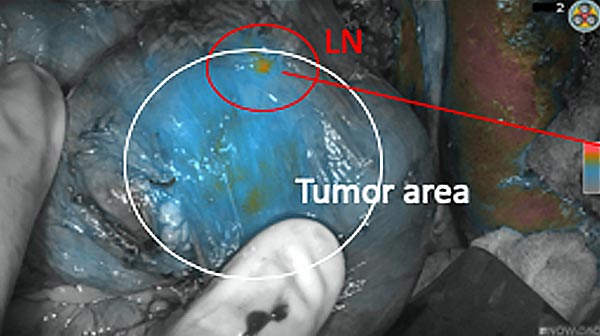

Intraoperative fluorescence imaging of the pancreas part that contains tumor

The tumor area light up fluorescently and so does a lymph node (LN; red circle) that is located on top of the tumor area. We can also see some lymphatic ducts (green circle).

After removal of the pancreas tumor fluorescence imaging was performed to check that there was no residual fluorescence left in the wound bed. A little bit of background fluorescence was found in the intestine.